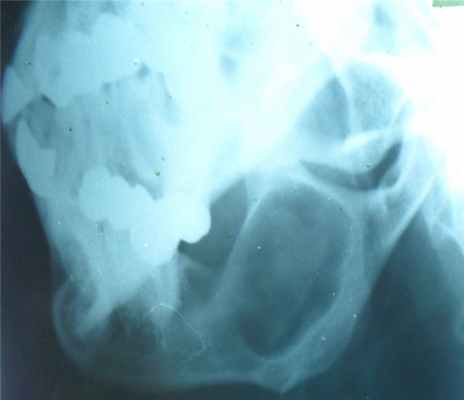

Прямая рентгенограмма таза и тазобедренных суставов.

Определяется резкая деформация тазового кольца. Правый тазобедренный сустав в норме. Выраженные изменения в левом тазобедренном суставе: суставная впадина углублена, суставная щель не прослеживается, головка деформирована с множественными очагами деструкции. Регионарный остеопороз, атрофия бедренной кости. Левосторонний туберкулезный коксит.